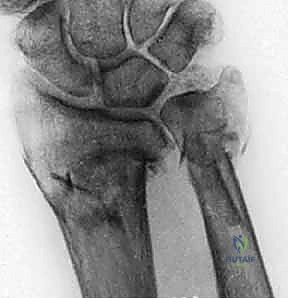

صورة طبية توضح كسر الناتئ الإبري

1. كسور الناتئ الإبري للزند (Ulnar Styloid Fractures)

الناتئ الإبري هو البروز العظمي الذي يمكنك الشعور به في الجزء الخارجي من معصمك.

* كسور قمة الناتئ الإبري (Tip Fractures): غالبًا ما تكون كسورًا قلعية (Avulsion fractures) صغيرة. عادة ما تكون مستقرة ولا تؤثر بشكل كبير على المفصل (DRUJ).

* كسور قاعدة الناتئ الإبري (Base Fractures): هي الأخطر. نظرًا لأن الأربطة الرئيسية للـ TFCC تتصل بقاعدة الناتئ، فإن الكسر هنا يعني غالبًا فقدان استقرار المعصم. يتطلب هذا النوع تقييمًا دقيقًا جدًا لمدى ثبات المفصل بعد تثبيت كسر الكعبرة (إن وجد).